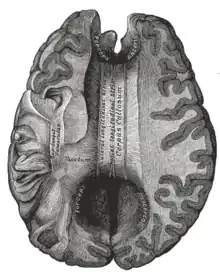

يسمى الجزء الخلفي من الجسم الثفني بالشريط؛ الجزء الأمامي يسمى الركبة؛ بين الجزئين ما يسمى بالجذع، أو "الجسم". غالباً الجزء بين الجذع والشريط ضيق بشكل ملحوظ وبالتالي يشار إليه ب "البرزخ". المنقار هو جزء من الجسم الثفني الذي يبرز للخلف وللأسفل من أكثر جزء أمامي للركبة، كما يمكن مشاهدته على الصورة السهمية للدماغ المعروضة على اليسار. المنقار سمي بذلك لأنه يشبه منقار الطائر. على كل جانب من الجسم الثفني، تنتشر الألياف في المادة البيضاء وتمر إلى مختلف أجزاء قشرة المخ؛ الألياف المنحنية للأمام من الركبة إلى الفص الأمامي تشكل الملقط الأمامي، والألياف المنحنية للخلف إلى الفص القذالي تشكل الملقط الخلفي. بين الملقط الأمامي والخلفي يكون الجزء الرئيسي من الألياف الذي يشكل البساط ويمتد جانبياً على الجهتين إلى الفص الصدغي، ويغطي الجزء الأوسط من البطين الجانبي. محاور عصبية رفيعة في الركبة تربط القشرة أمام الجبهية بين نصفي الدماغ؛ هذه الألياف تنبثق من حزمة من الألياف تشبه الشوكة من البساط، الملقط الأمامي. المحاور العصبية الأثخن في منتصف الجسم الثّفَني أو في جذع الجسم الثفني، تربط مناطق القشرة الحركية، وبتناسب الكثير من الجسم الثفني المكرس بشكل إضافي للمناطق الحركية بما في ذلك باحة بروكا. الجزء الخلفي من الجسم الثّفَني؛ المعروف بالشريط، ينقل معلومات حسية جسدية بين نصفي الفص الجداري والقشرة البصرية في الفص القذالي، هذه هي ألياف الملقط الأمامي.[2][3]

بطينات الدماغ والعقد القاعدية. منظر من الأعلى قطع أفقي .تشريح عميق

بطينات الدماغ والعقد القاعدية.مشهد من الأعلى قطع أفقي .تشريح عميق

المخ. مشهد من الأسفل. تشريح عميق